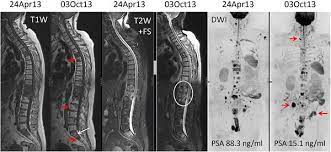

The hormones that your thyroid gland produces help regulate several of your bodily functions. Prostate cancer is one of the most common types of cancer diagnosed in men. Can bone metastasis happen in the prostate cancer? The earlier the detection of prostate cancer, the better the patient's chance of survival is. Prostate cancer is a common type of cancer in men, according to the mayo clinic.

The earlier the detection of prostate cancer, the better the patient's chance of survival is. One in seven men in the united states will receive a prostate cancer diagnosis during his lifetime. If you have been diagnosed with adenocarcinoma cancer, you have a cancer that developed in one of the glands that lines the inside of your organs. These include your blood pressure, heart rate and metab. Prostate cancer is one of the most common types of cancer diagnosed in men. Find the information you need today. The hormones that your thyroid gland produces help regulate several of your bodily functions. The american cancer society provides detailed information on prostate cancer and its treatment. Prostate cancer is a common type of cancer in men, according to the mayo clinic. Here are 10 more facts about prostate cancer. The pancreas is a bodily organ that few people think about. Can bone metastasis happen in the prostate cancer? According to the american cancer society, a.